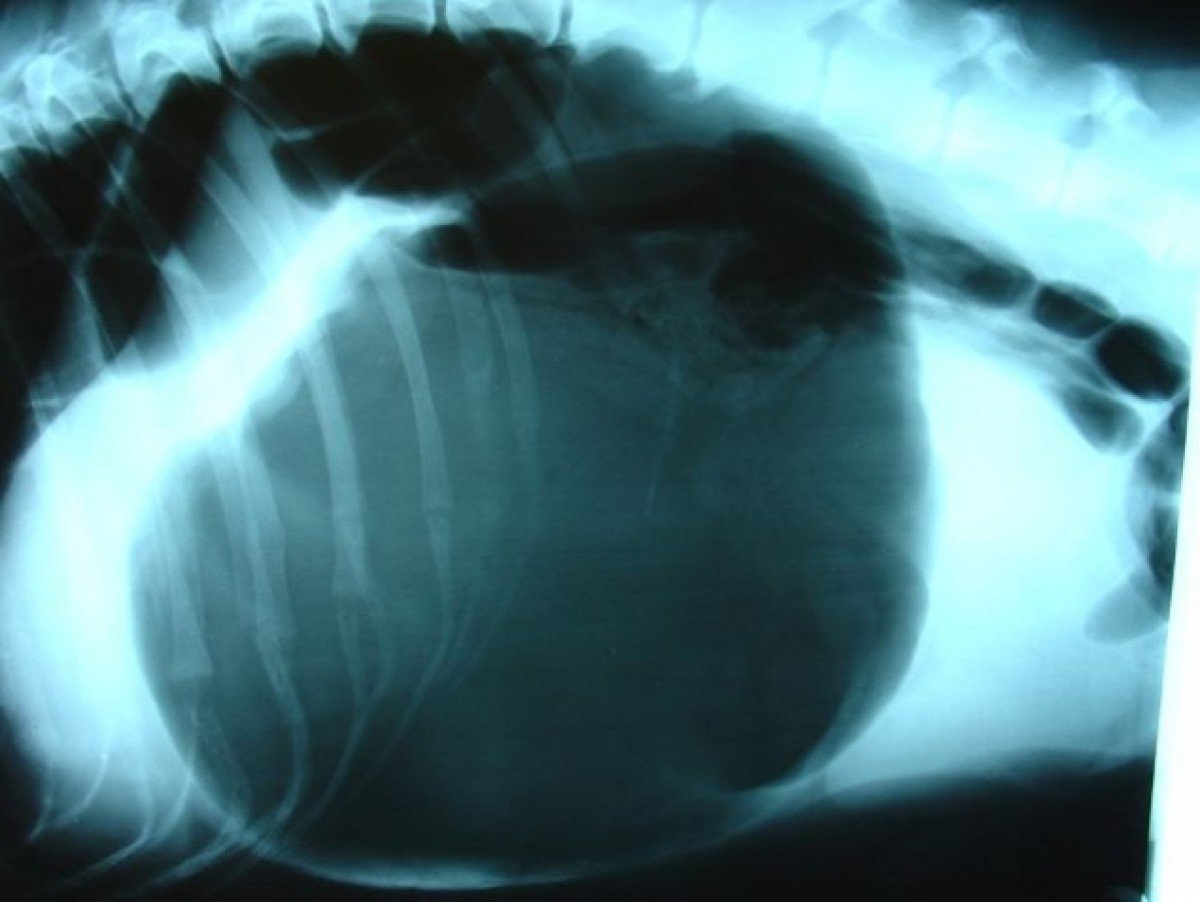

Oricine isi doreste gemeni dar cand pruncii din burta sunt mai multi, sarcina devine un cosmar. Cea mai frumoasa perioada dar si cea mai grea din viata unei femei s-a transformat pentru o tanara din Anglia intr-o trista poveste.

Vestea data de medici a luat prin surprindere o familie din Anglia iar faptul ca vor deveni parinti a nu mai putin de 8 copii i-a coplesit pur si simplu pe cei doi. Desi numarul lor era neobisnuit de mare viitorii parinti erau extrem de fericiti si astemtau cu nerabdare momentul in care micutii vor veni pe lume.

Totul s-a terminat tragic. Femeia a pierdut sarcina din cauza unor comlicatii. Toti pruncii au murit pe parcursul a trei zile iar viata tinerei femei s-a transformat intr-un cosmar. Mandy Allwood a incercat sa se sinucida de doua ori. Din fericire tanara a trecut peste perioada grea din viata si acum isi doreste din nou sa devina mama.